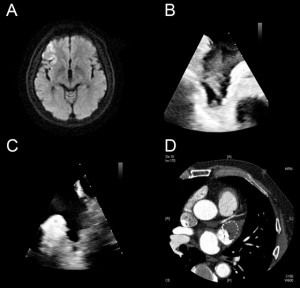

<Abstract:> Some patients develop ischemic stroke despite taking direct oral anticoagulants because of the presence of other risk factors such as coagulopathies. A 65-year-old male patient with non-valvular atrial fibrillation (NVAF) taking rivaroxaban was diagnosed as having embolic stroke and antithrombin-III (AT-III) deficiency. Echocardiography revealed a thrombus in the left atrial appendage (LAA). He was prescribed warfarin, and after resolution of the thrombus, we successfully performed percutaneous LAA closure (LAAC), with no subsequent recurrence or device-related thrombosis. Warfarin and LAAC may be feasible for NVAF patients with AT-III deficiency.